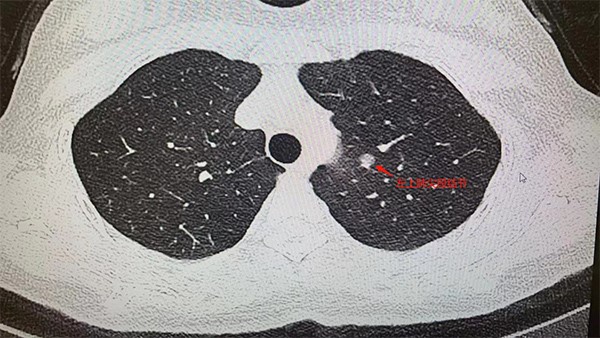

據(jù)了解,王女士今年5月在重慶市某三甲醫(yī)院做例行體檢時(shí),低劑量胸部CT顯示:左肺上葉尖后段有7mm*6mm的磨玻璃結(jié)節(jié),性質(zhì)待定。醫(yī)生表示有肺癌可能性,建議進(jìn)一步診治。肺結(jié)節(jié)這么小,到底切不切?10月24日,王女士來到重慶西區(qū)醫(yī)院胸外科主任姚珂門診隨訪。

姚珂介紹,結(jié)合影像學(xué)特征,王女士的肺小結(jié)節(jié),惡性征象明顯。制定手術(shù)方案時(shí),姚珂考慮到該患者病灶靠近主支氣管,位置較深,需要游離的血管較多,為保證精準(zhǔn)切除病灶且最大程度保護(hù)患者肺功能,通過穿刺定位+CT三維重建引導(dǎo),行單孔胸腔鏡下肺聯(lián)合亞段切術(shù),最為合適。目前,手術(shù)取得成功。

患者胸部CT檢查圖片。重慶西區(qū)醫(yī)院供圖